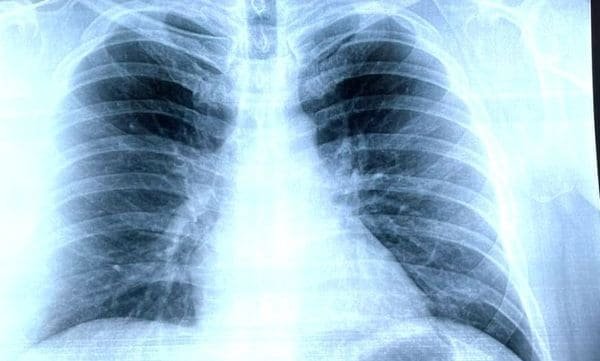

Знімок легень при пневмонії

Знімок легень при пневмонії… Основа, за якою визначають діагноз, оцінюють стан, вирішують долю лікування. Взагалі, рентгенологія перевернула світ медицини, але чому? Що такого особливого в цих знімках, де бронзи та скарби здоров’я? Давайте розбиратися.

Як виглядає знімок легень при пневмонії

І от, коли ви отримали свій знімок легень при пневмонії — що ви бачите? Чорні і білі контури. Немов старе кіно, цей знімок відкриває театральність внутрішнього світу. Але … його мова специфічна.

Типові ознаки на знімку

- Поява “білих” зон, які свідчать про запальний процес.

- Зміни у формі та розмірах легень.

- Видимі розмиті границі легень.

Ці деталі говорять досвідченому очу фахівця більше, ніж десятки слів пацієнта.